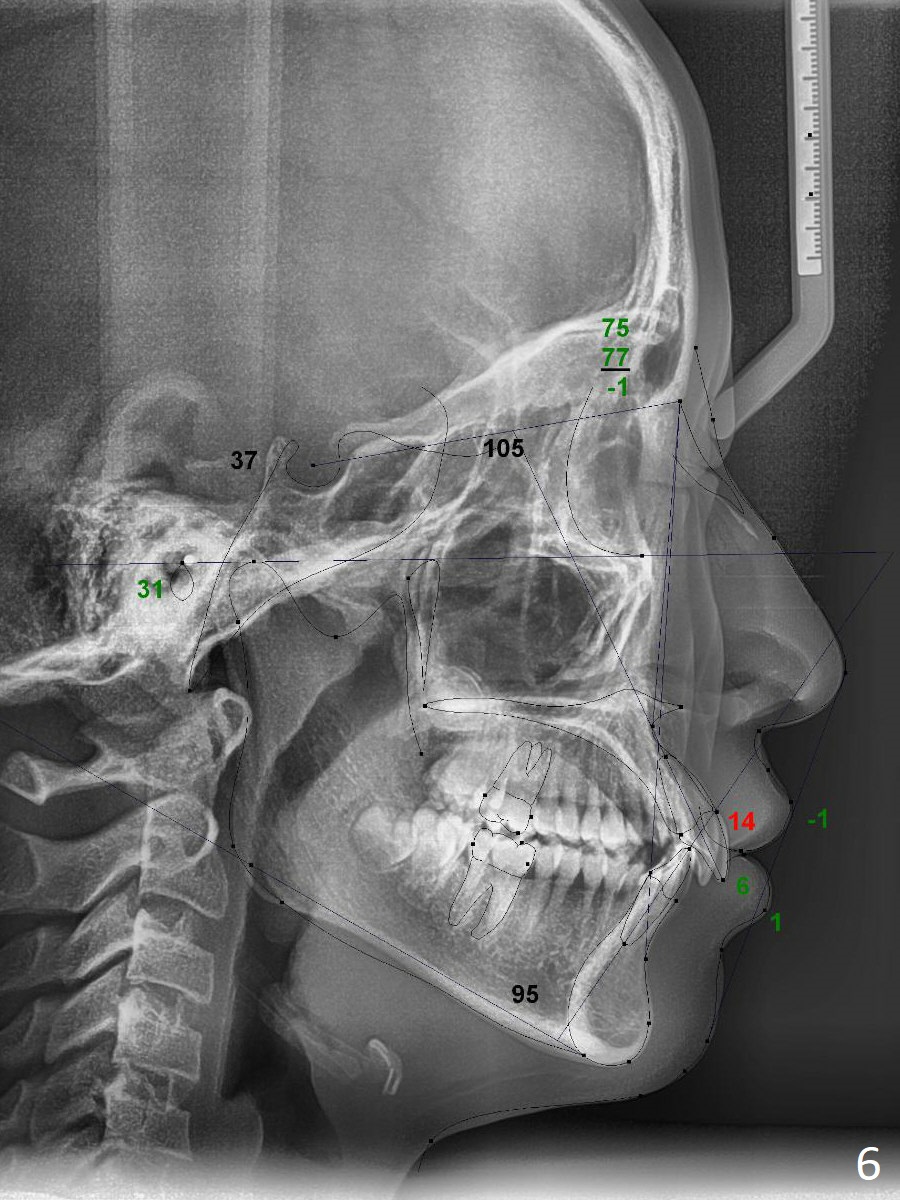

A 12-year-old woman has normal facial profile (Fig.1-6,12) and crowded dentition (7-11). Because of erupting 2nd molars (Fig.10,15), it is difficult to place rubber separators between U6/7. Copper ones are used instead (Fig.15 ^). Crowding and narrow arches (Fig.13,14) may be associated with the enlarged right Inferior Nasal Concha (Fig.15 *).